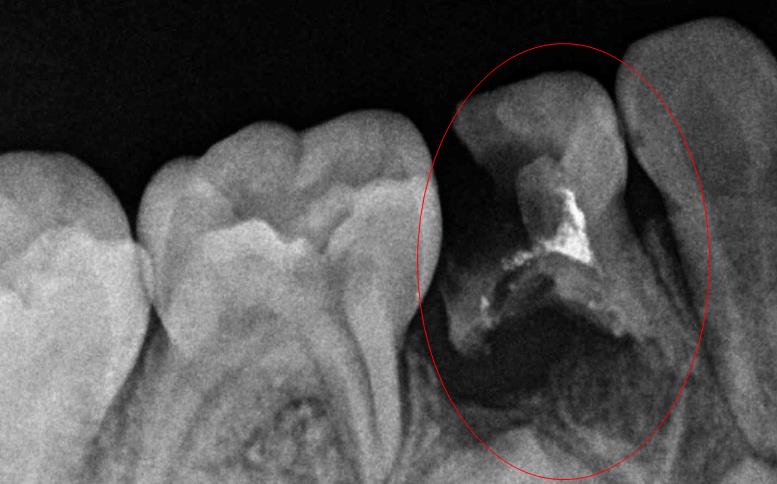

看紅圈內(nei) 的牙齒幾乎全部齲壞了

補牙前,可能需要拍小牙片(幾十一百塊左右)來確定齲壞程度,確定有沒有齲壞到牙齒中間的牙神經,如果沒有,就還好,可以去除壞掉的牙齒後用人工材料充填好,這種方式簡單,沒有痛苦,過程也就半個(ge) 小時到一個(ge) 小時左右,價(jia) 格根據補牙材料,常規的三四百元左右,如果性能更好的材料價(jia) 格可能更貴一些。

但是如果小牙片顯示齲壞到牙神經或者以及下行感染到牙根了,這下就沒法直接補牙了,還需要先把感染的牙神經先去除,不然急性牙髓炎引起的疼痛沒有幾個(ge) 人能承受得了,先把牙神經去除止痛後再治療。牙神經去除後疼痛緩解了,再對牙根裏麵壞掉的感染物質一一去除幹淨(一定要去除幹淨),去除幹淨後再用材料把牙齒充填起來,這種方法叫做根管治療,過程比較複雜,價(jia) 格也要兩(liang) 三千左右一顆。